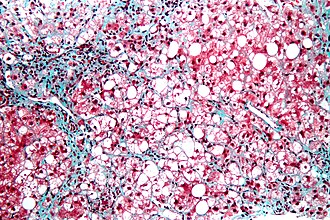

Steatohepatitis. Trichrome stain. | |

| LM | steatosis (usually macrovesicular); hepatocyte injury -- ballooning degeneration (key feature), Mallory bodies; portal bridging (late stage) |

C. Steatohepatitis. Brunt necroinflammatory grade 1. Brunt fibrosis stage 1.

Steatohepatitis. Brunt necroinflammatory grade 1. Brunt fibrosis stage 1. A. Steatosis afflicts about 30% of hepatocytes; note the absence of visible triads. B. Cytoplasmic tufts of ballooning degeneration [violet arrows] were commonly found; a lymphohistiocytic aggregate [blue arrow], important for NAFLD, but not for Brunt, is seen. C. A triad shows a vein [green arrow], an artery [red arrow], an interlobular duct [blue arrow], and proliferating bile ductules [cyan arrows]; only a few lymphocytes are seen . D. Central vein shows only a few endothelial cells, with somewhat packed hepatocytes surrounding it. E. Trichrome shows mostly space of Disse fibrosis [black arrows], sometimes adjoining hepatocytes [green arrows] show this is a stage 1 fibrosis. F. Trichrome shows a central vein with a minimum of sclerosis; an interhepatocyte fibrous extension [arrow] displays the very beginning of fibrosis.